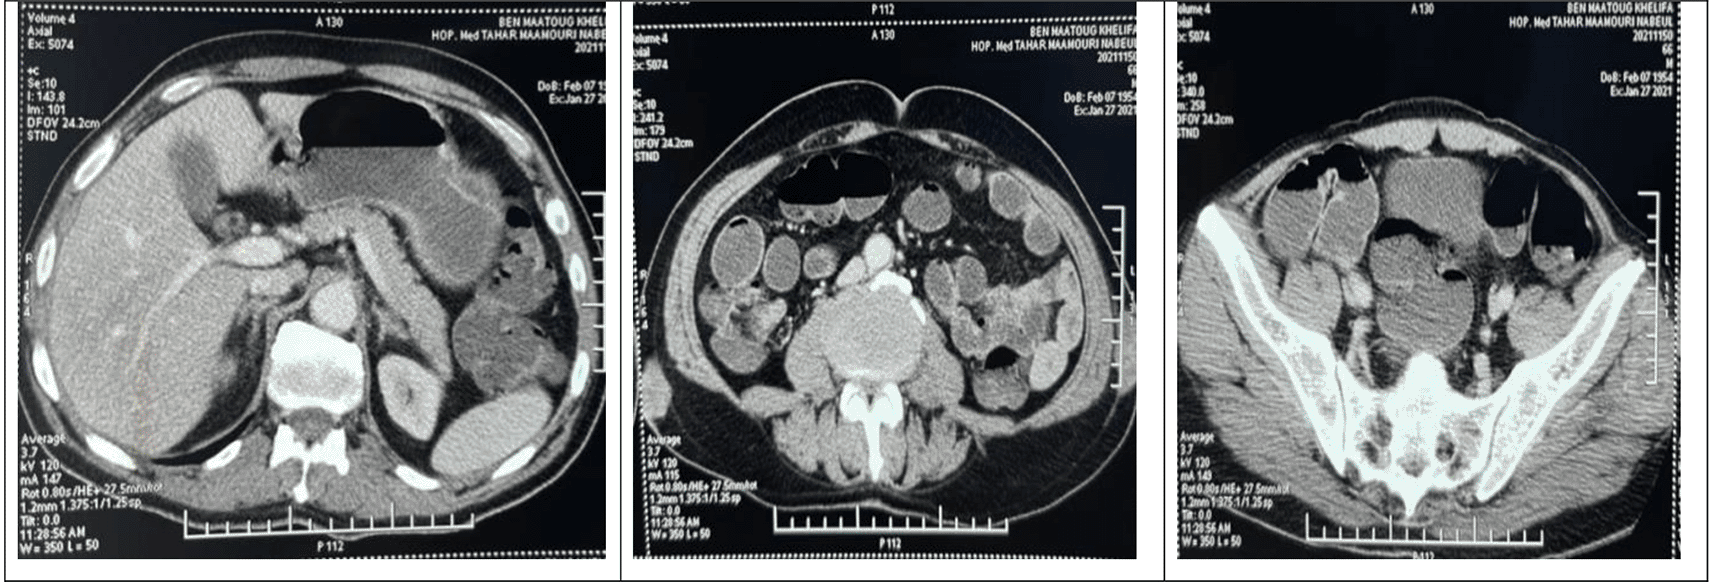

A computed tomography (CT) scan, performed as part of the extension assessment, showed the presence of a left apical sub-pleural nodule of 3 mm diameter, subcutaneous nodules on the right and left flanks and on the right posterior chest wall measuring 28 * 22 mm, 36 * 18 mm and 18 * 9 mm, respectively. They were associated to masses with heterogeneous contrast enhancement of the right gluteus maximus and left gluteus medius muscles (Figure 3).